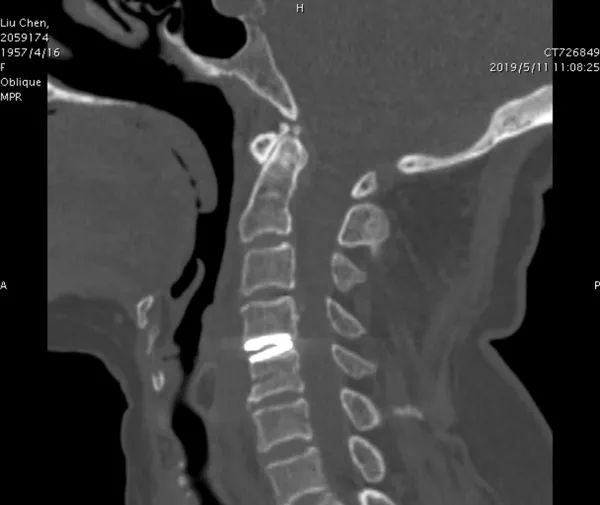

日前,西安市红会医院脊柱外科团队实施全球首例3D打印人工颈椎间盘置换术获成功。为患者量身制定个体化的人工颈椎间盘,最大限度保留患者颈椎的活动度,并有效降低术后相关并发症的发生,被誉为医疗界的“硬科技”。

今年52岁的患者刘女士来自陕西省洛南县,5个月前出现了左上肢胀痛、麻木和无力症状,且伴有走路不稳。经过详细检查,医生发现刘女士颈4/5巨大椎间盘突出。采访中,院长郝定均说:“患者年龄不大,颈椎稳定性好,颈椎退变增生不严重,颈椎间盘突出节段少。如果按常规给她实施颈椎间盘减压融合术,固定节段活动度丧失,术后可能出现临近节段退变而需要再次手术治疗,后续治疗曲折,得不偿失。”由此,3D打印技术被提上方案。

3D打印“零件” 人工颈椎间盘置换获成功

红会医院脊柱病医院退变与肿瘤病区主任单乐群表示,3D打印人工颈椎间盘假体是基于患者的影像资料,先重建患者自身的颈椎3D图像,再根据图像资料设计并量身定制出最符合患者的个性化假体,3D打印出来假体后应用于患者手术。

3D打印人工颈椎间盘置换,可为每一位患者量身制定个体化的人工颈椎间盘,从而有效降低术后相关手术并发症的发生。

术后第3天,刘女士就可以借助家人搀扶下地行走,困扰已久的左上肢胀痛、麻木、无力及行走不稳的症状明显改善。术后第5天,刘女士就在颈托保护下自由行走了。